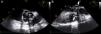

While awaiting surgery a new-onset systolic-diastolic murmur was noted. The echocardiogram performed at that time revealed marked paravalvular involvement of the prosthetic valve with multiple larger abscesses (Figure 3A and 3B, asterisks) surrounding the anterior, posterior and right portions of the prosthesis (Figure 3A and 3B, cross) which communicated with the left ventricular outflow tract, forming a pseudoaneurysm that extended 3 cm above the aortic valve plane (Figure 3C, white arrows). Severe periprosthetic regurgitation was also noted (Figure 3D) and the patient underwent cardiac surgery. Meanwhile, microbiological study revealed the presence of Streptococcus milleri sensitive to the empirically started antimicrobial therapy. Interestingly, the patient had a history of ingestion of a bone fragment that had been removed from the esophagus by upper gastrointestinal endoscopy 2–3 weeks before the beginning of the constitutional symptoms. This event was the most probable portal of entry for the bacteremia. Unfortunately, the patient died in the perioperative period due to surgical complications.

Transesophageal echocardiogram showing multiple abscesses (asterisk) surrounding the single-disc mechanical prosthetic valve (cross). These abscesses had ruptured to the left ventricular outflow tract forming a pseudoaneurysm (white arrow) extending above the aortic valve plane. Severe periprosthetic regurgitation and mild to moderate mitral regurgitation were also noted (D). The images were obtained in mid-esophageal view at 0° (A); short-axis view (B); and long-axis view without (C) and with (D) color flow Doppler.